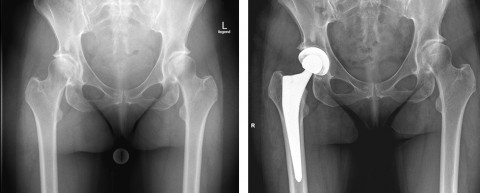

Fall 2: 60-jährige Patientin mit einer sekundären Arthrose der rechten Hüfte

Die sekundäre Arthrose der rechten Hüfte war durch eine Reifungsstörung des Hüftgelenkes (Dysplasie) bedingt. Die linke Seite war ebenfalls betroffen, jedoch weniger schmerzhaft. Durch die besondere Form des Oberschenkel-Knochens, welcher relativ steil zur Pfanne ansteigt (Valgus), war die Wahl eines Implantates erforderlich, das die entsprechende Anatomie berücksichtigt. Die Operation konnte in minimalinvasiver Technik erfolgen, durch die Wahl des korrekten Implantates wurde die patientenindividuelle Anatomie berücksichtigt.